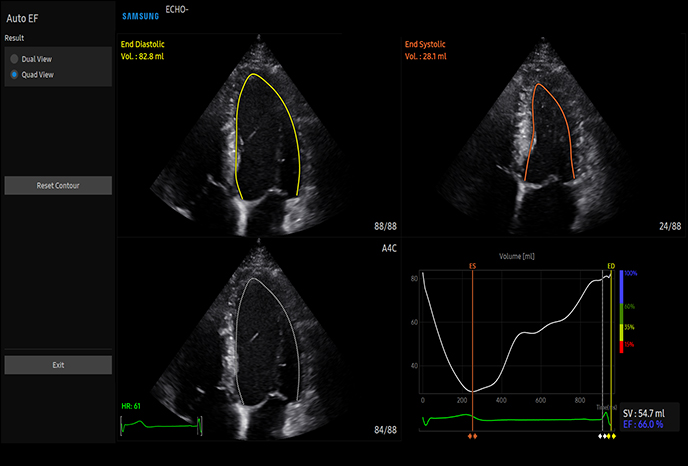

자동 EF(박출률) 계산

고급 실시간 3D(4D)로 시각화 가능

고급 도플러 기능으로 심혈관 평가 및 이상 감지

심장심장의 해부학 구조 및 혈류역학적 평가, 순환기계 장애, 심장 수축·이완